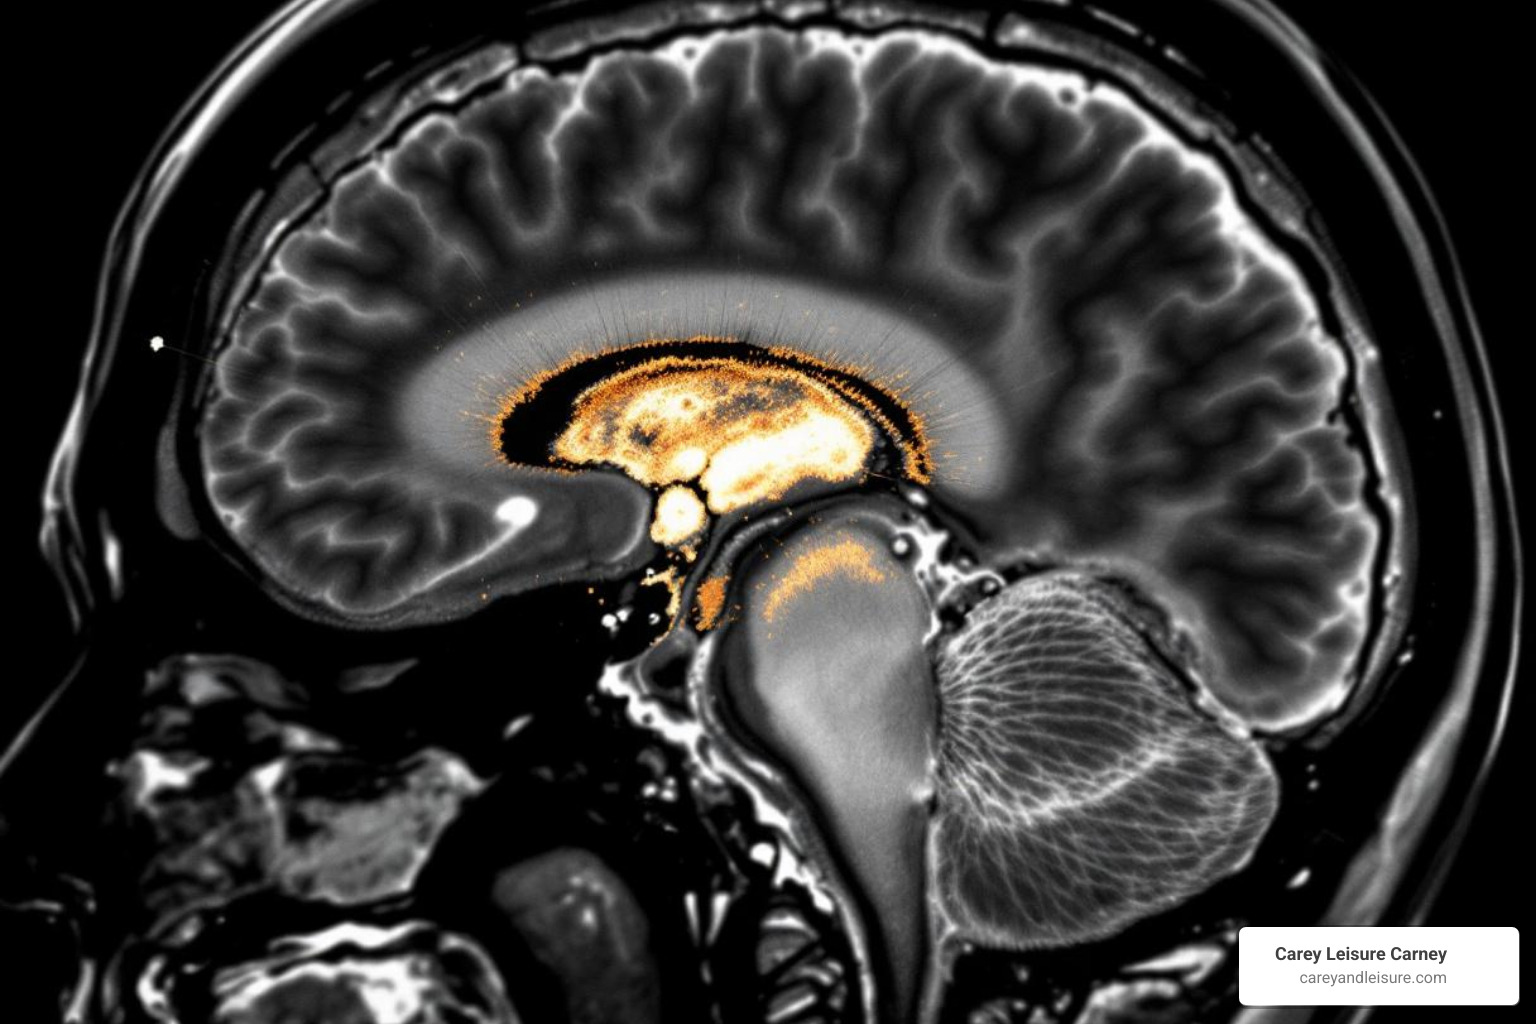

An experienced attorney for brain injury understands the medical nuances of these cases. They know how to interpret complex medical records, understand diagnostic tests like CT scans and MRIs, and recognize subtle signs of brain dysfunction that might be missed by a general personal injury lawyer. This medical understanding is crucial for proving the nature and extent of the injury, as well as its long-term implications.

Proving causation in brain injury cases is particularly complex, especially with mild TBIs where symptoms can be subtle or delayed. This is where the role of evidence becomes paramount. We gather extensive medical records, including initial emergency room reports, neurological evaluations, diagnostic imaging (CT scans, MRIs, fMRIs), and rehabilitation notes. Witness statements, accident reports, and expert opinions from various medical and vocational specialists are also crucial. These experts help connect the dots, explaining how the negligent act led to the injury and detailing its profound impact on your life.